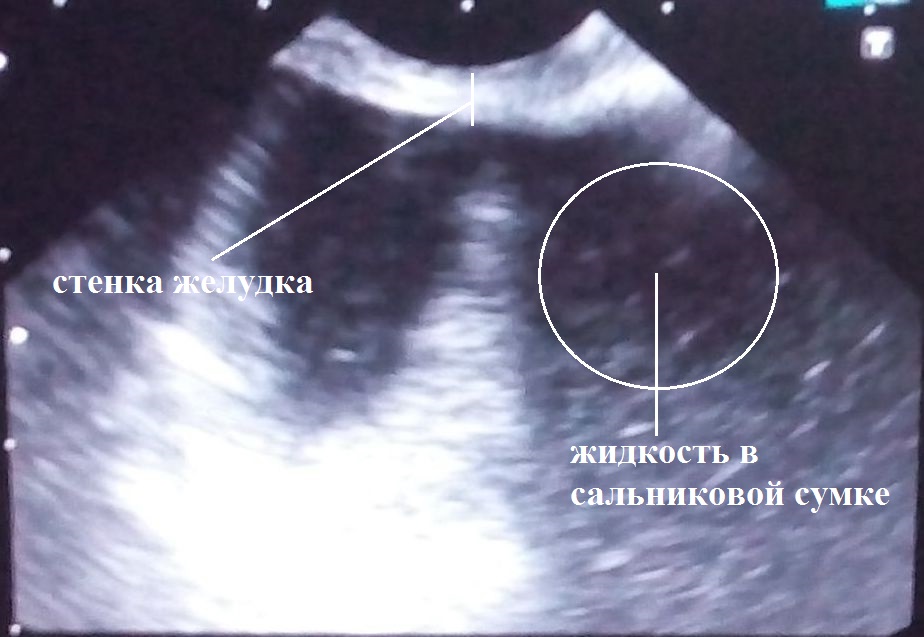

Пациент М., 69 лет, поступил в клинику 21.09.2017 г. на первые сутки от начала заболевания. При клинико-инструментальном обследовании установлен предварительный диагноз: острый тяжелый панкреатит, оментобурсит (рис. 1).

Начато консервативное лечение согласно клиническим рекомендациям. В ходе динамического инструментального (УЗИ, КТ) контроля на 8-е сут выявлено формирование острого жидкостного скопления (ОЖС) в сальниковой сумке (рис. 2). На 13-е сут заболевания, 04.10.2017 г., появились признаки инфицирования ОЖС — повышение температуры тела до 38,5 °С, лейкоцитоз до 11,3 × 109/л, С-реактивный белок — 156 мг/л, что явилось показанием к оперативному вмешательству.

Под контролем эндосонографии 04.10.2017 г. выполнено эндоскопическое цистоназальное трансгастральное дренирование ОЖС сальниковой сумки с установкой цистоназального дренажа диаметром 5 Fr и цистогастрального дренажа типа double PigTail диаметром 7 Fr (рис. 3).